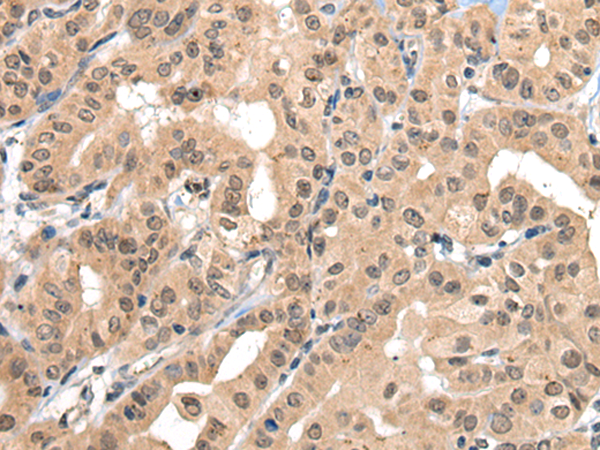

IHC positive control:

Human thyroid cancer and human colorectal cancer

IHC Recommend dilution:

30-150